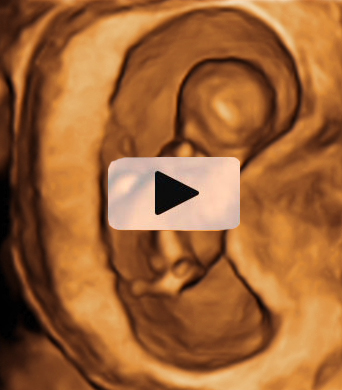

Ecografía Embarazo 2D y 3D Semana 12 - PRUEBAS DIAGNÓSTICAS